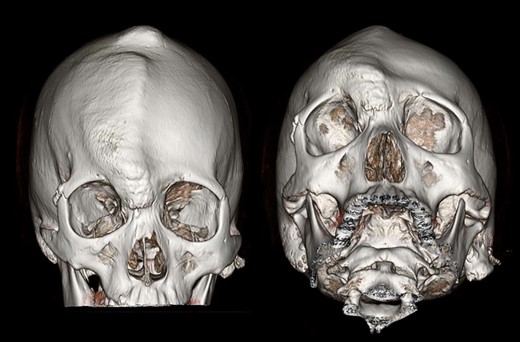

A 17-year-old girl referred to us with a chief complain of a painless bump on her right forehead. She also had a projection on the parietal area. She and her family told that the protrusions had been observed since she was below teenage and had not changed for these 3 years. She had no visual impairment. She felt healthy and self-reported no other abnormality. X-ray computer tomography scan showed osseous hypertrophic lesions in frontal and parietal bone (Figs 1 and 2). Ground glass appearance of diploe implied fibrous dysplasia. Frontal sinus was dilated without mucosal hypertrophy or frontonasal duct stenosis. Multiple intra-cranial calcification was observed. She presented no psychomotor disorder.

Three-dimensional CT of the patient’s skull. Protrusion of right frontal and parietal area was well observed.